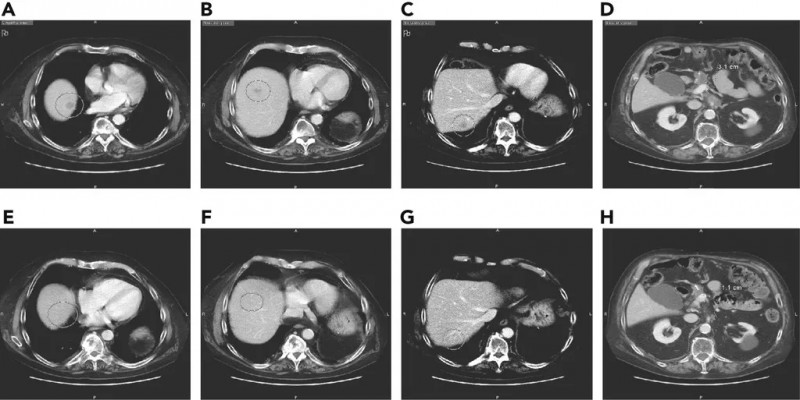

用曲美替尼和羟氯喹治疗移植了胰腺肿瘤的小鼠,结果显示肿瘤一致消退。

这名患者接受了 trametinib和hydroxychloroquine治疗,令患者和医生震惊的是,奇迹出现了,2个月内,患者的胰腺癌标志物CA 19-9的血液水平下降了95%。4个月后,他体内的癌症数量减少了50%。

用曲美替尼加羟氯喹(T / HCQ)治疗胰腺癌患者导致肿瘤标志物癌抗原19-9(CA19-9)和总体肿瘤负荷减少。